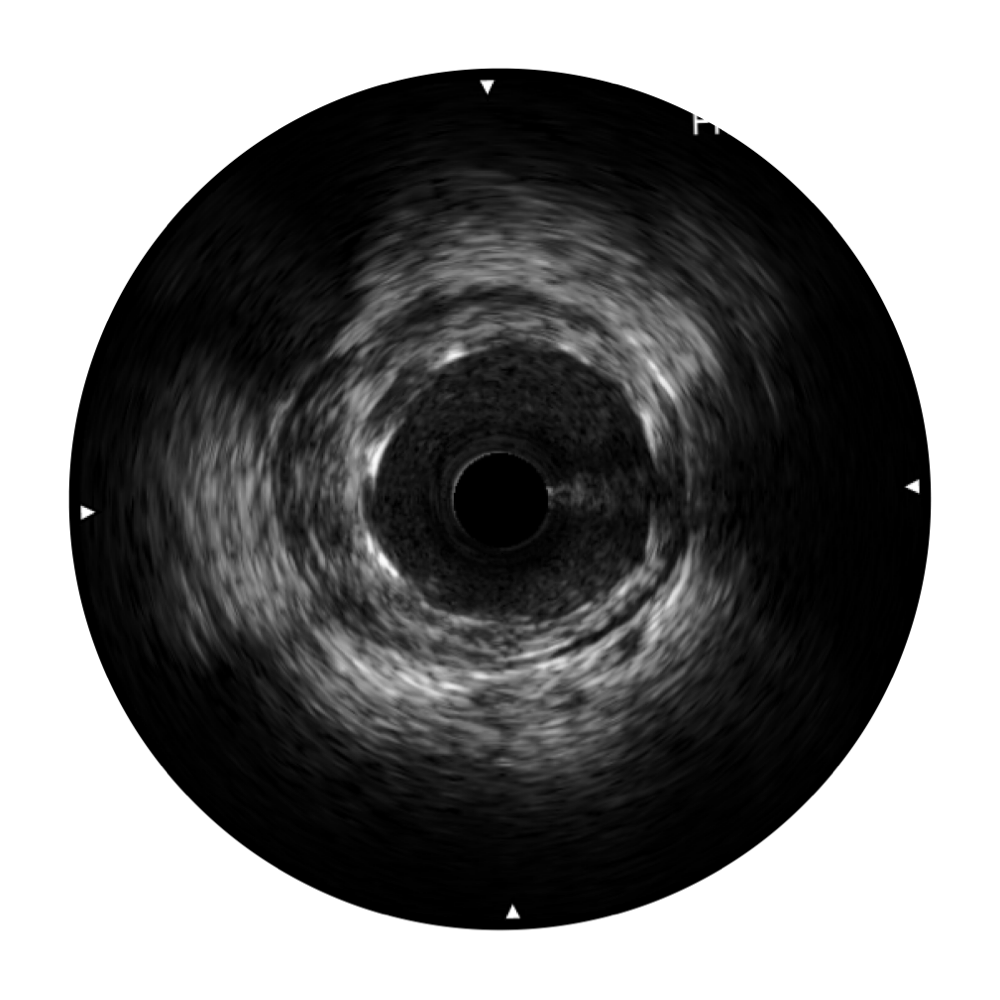

传统IVUS图像

对比传统IVUS导管成像,云顶集团官网宽频IVUS图像的近场支架梁显影更细腻,远场中膜外血管仍清晰可辨,兼顾远中近,兼顾分辨力与穿透深度